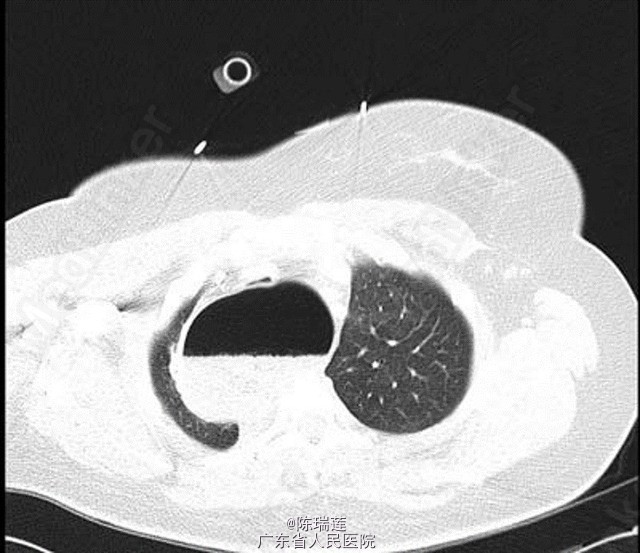

体检发现,患者呼吸急促,但无明显哮鸣音。急救人员初步考虑为哮喘急性加重,给予激素雾化吸入和静脉使用,但症状无好转。 急诊行胸片示右上肺透亮影(图 1)。 行肺部 CT 示食管内有大量食物,呈显著扩张状态;严重压迫气管及气管内插管(图 2)。拔管后行胃十二指肠镜检查,未发现存在梗阻。

诊断:巨食管症 处理:到达医院急诊时,患者呼吸困难症状进一步加重,出现呼吸暂停。即刻给予气管插管和呼吸机辅助通气。给予放置鼻胃管,引流出大量胃内容物。拔管后行胃十二指肠镜检查,未发现存在梗阻。患者诊断为巨食管症,后转入一家三级医院行肌层切开术治疗。

随访:后转入一家三级医院行肌层切开术治疗。 讨论:巨食管症导致气管受压是贲门失弛缓症的罕见临床变现。追问病史发现,患者无哮喘病史,但既往明确诊断有贲门失弛缓症。患者最近几周自觉饭后常出现胸部不适及明显反流症状。虽然患者至急诊时已出现呼吸暂停,个人不能提供病史,但本病例的诊断明确显示了询问病史的重要性。